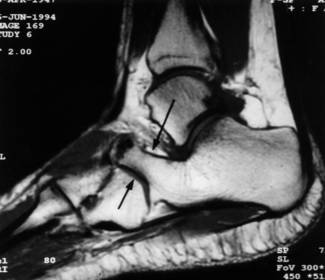

This patient has taken a short course of prednisone. What does the image show? | Osteonecosis of the talus |

What does this image show? | Avascular necrosis of the talus, secondary to a talar neck fracture |